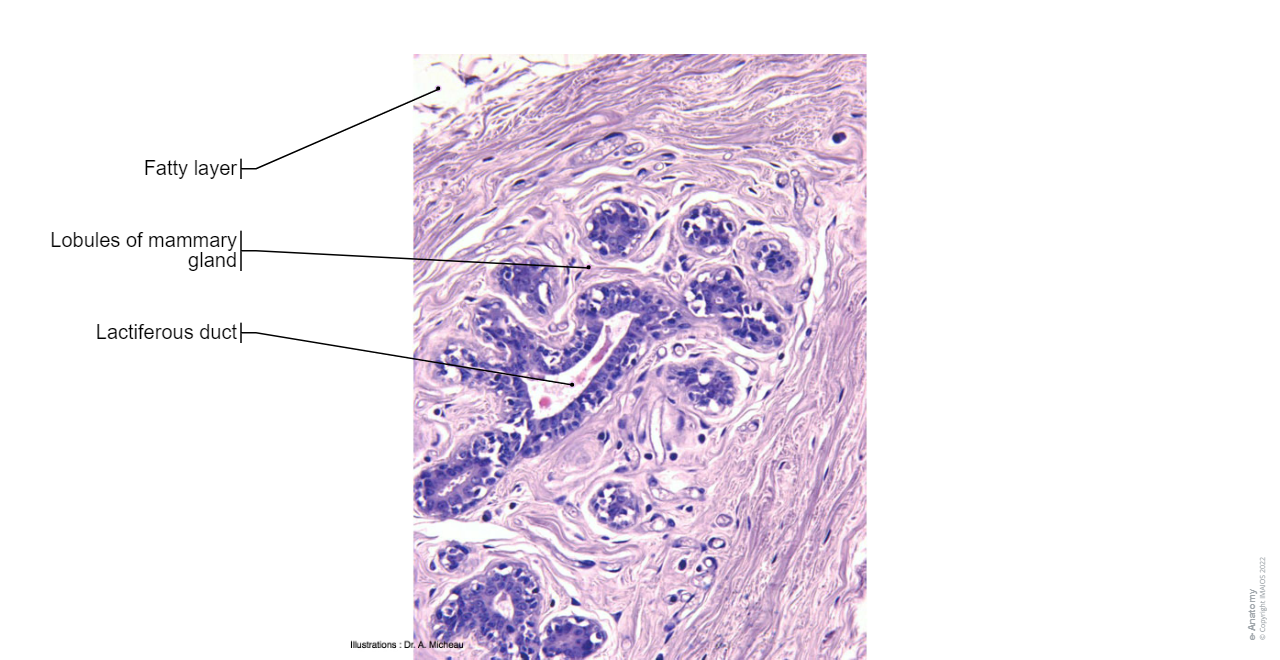

•  Breast: several illustrations represent the surface anatomy of the mammary gland (nipple, areola, axillary process), the sagittal anatomy of the breast (lobes, lactiferous sinuses, milk ducts), the arterial and venous vascularisation, the lymphatic drainage and histology of the breast.

Breast - Histology : Mammary gland,Lobes of mammary gland, Lobules of mammary gland, Lactiferous duct, Lactiferous sinus